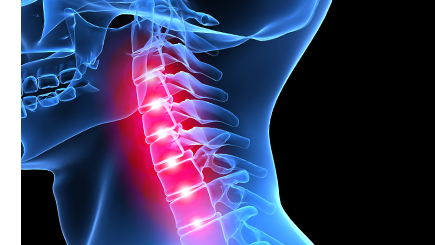

뒷목이 뻣뻣하고 목의 움직임이 제한되며, 두통, 어깨, 팔, 손까지 통증이 나타날 수 있습니다.

위 증상 중 한가지라도 해당된다면 “목 디스크”일 수 있습니다.

경추 내부 수액이 빠져나오며 신경근, 척수를 누르며 통증이 발생합니다. 퇴행성 변화, 사고, 잘못된 자세의 습관화가 목디스크의 주요 원인입니다.